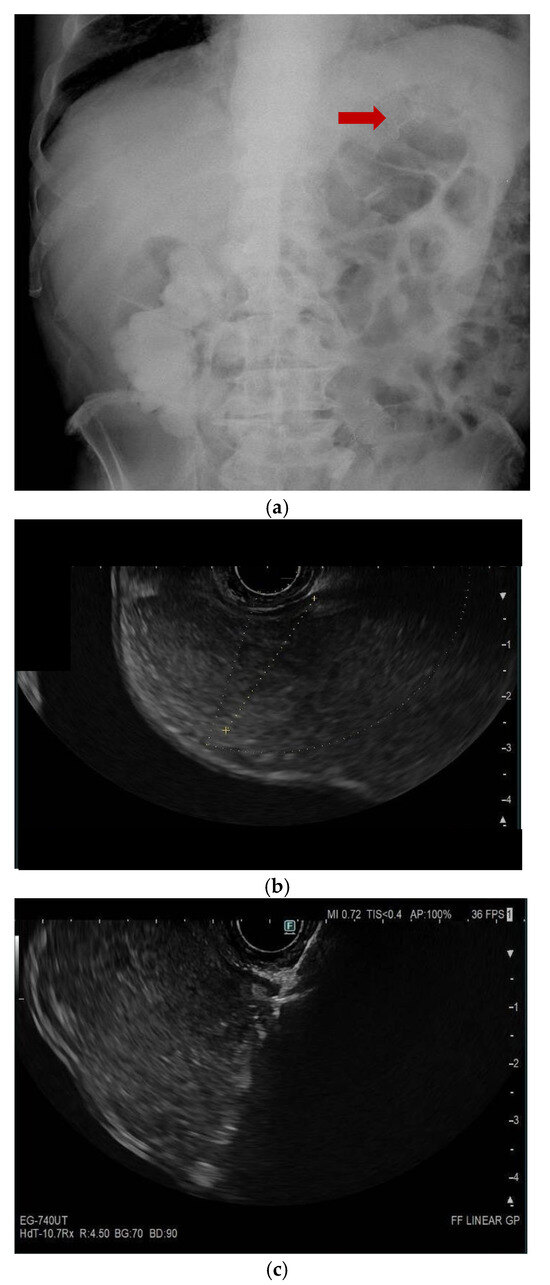

10. Endoscopic Ultrasound-Guided Entero-Colostomy with LAMS

- Neri, B.; Stigliano, S.; Biasutto, D.; Citterio, N.; Lisotti, A.; Fusaroli, P.; Mangiavillano, B.; Donatelli, G.; Tonini, G.; Di Matteo, F.M. Endoscopic ultrasound-guided entero-colostomy with lumen-apposing metal stent as a rescue treatment for malignant intestinal occlusion: A multicenter study. Endoscopy 2025, 57, 77–82. [Google Scholar] [CrossRef]